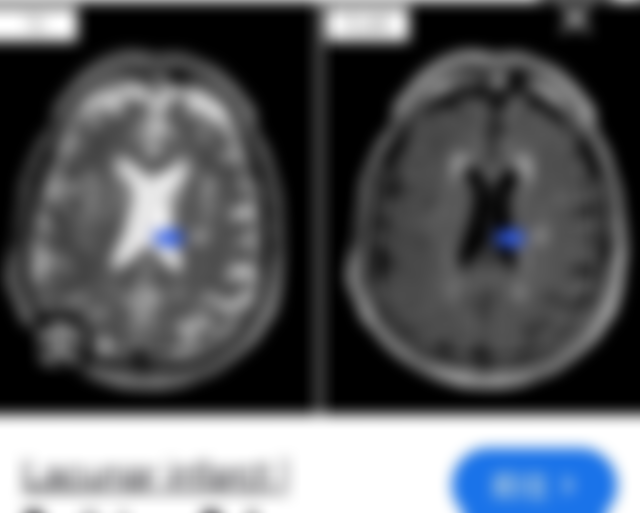

33.中風男性的核磁共振影像如下圖所示,最有可能的診斷為何?

(C) 中大腦動脈梗塞型中風